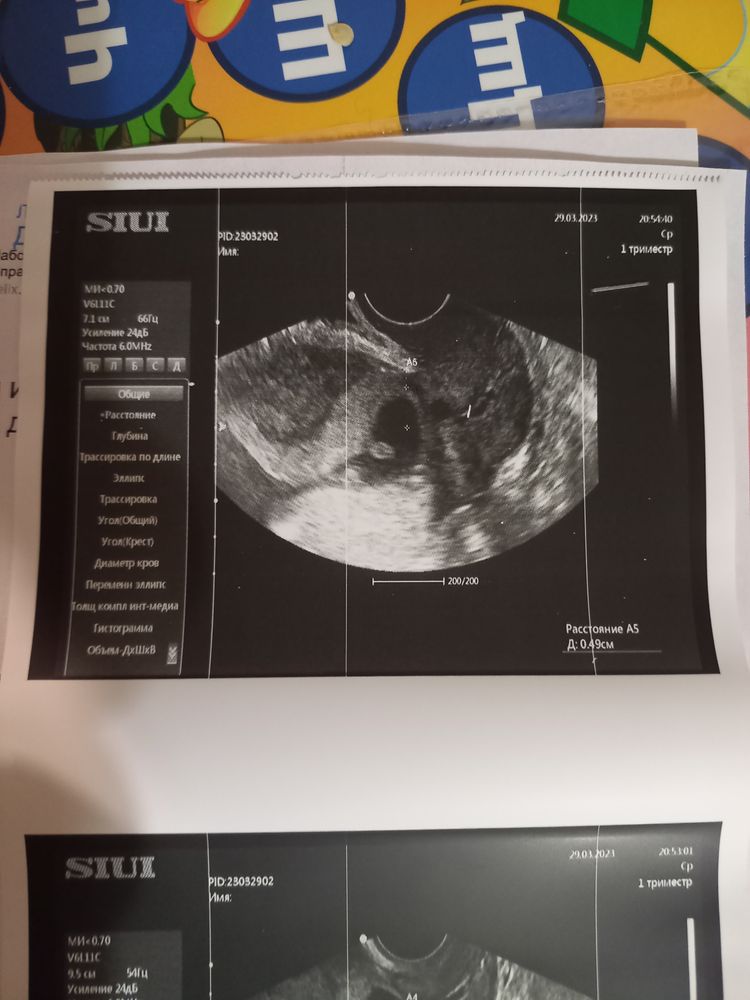

,думала,что все нормально будет и все тонусы уйдут,но сегодня и по передней и по задней стенке тонус.Бедный малышуля как будто зажат там.Сердечко бьется-ЧСС-161/мин.Но переживаю сильно по поводу этого расширения.Доктор говорит-впринципе ничего критичного,контроль узи-скриннинг в 12 недель.А в выписке написала:"УЗ-угроза невынашивания".Девочки,все ведь не так критично?

Lena Fried, вот на этих снимках доктор показывала мне,все по отдельности:на одном-плодное яйцо деформированное,на другом-сердечко,на третьем-как раз вот это цервикальный канал.Короче,надо бежать к гинекологу срочно

Был тоже просвет по всему каналу но меньше. 1.6мм. Для повторнородящих это в порядке нормы считается. У вас есть реальная угроза. Гинеколог должен будет решить что делать и как вам помочь. Не напрасно вы переживайте. Тонус часто увеличивается во время узи но опять же смотря какой тонус. Надо принимать меры короче. Смотрю вот а форма пя неправильная. Ничего не говорила врач? Или это следствие тонуса? Плодное яйцо на 10недель эмбриона на 7 недель. Вы пишите про 8 недель. Что то я ниче не пойму